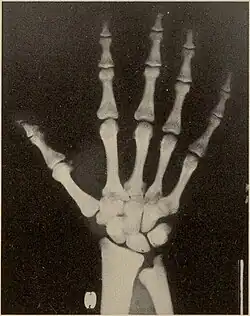

X-rays of the head and hand in pycnodysostosis, showing open fontanelle and shortened distal phalanges

Pycnodysostosis causes the bones to be abnormally dense; the last bones of the fingers (the distal phalanges) to be unusually short; and delays the normal closure of the connections (sutures) of the skull bones in infancy, so that the "soft spot" (fontanelle) on top of the head remains widely open.[9] Because of the bone denseness, those with the syndrome suffer from fractures.[7]